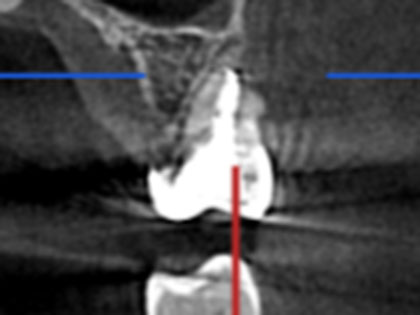

• 術前の写真がこちら

• 歯根端切除の術前3

• 歯根端切除の術前4